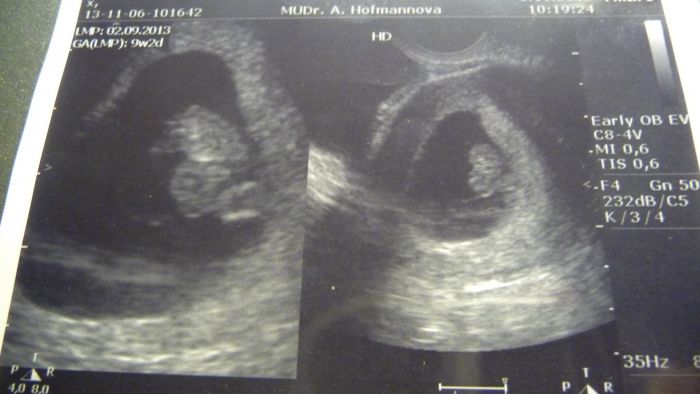

Musím se pochlubit fotem

, ale bohužel nám nejde scanner, tak jsem to fotila foťákem a není to ono, ale tu naší fazolku už uvidíte.

[386089] téda, vždyť ji máš krásnou!! i ty barvy... a pochopila jsem správně, že máš 1,65 cm ? tak to mám skoro i já.. máme 1,62 cm. V jakém jsi týdnu? Mě Dr. řekla, že jak jsem měla nepravidelnou MS, tak se to pozná až déle. Gratuluji, krásná bublinka..